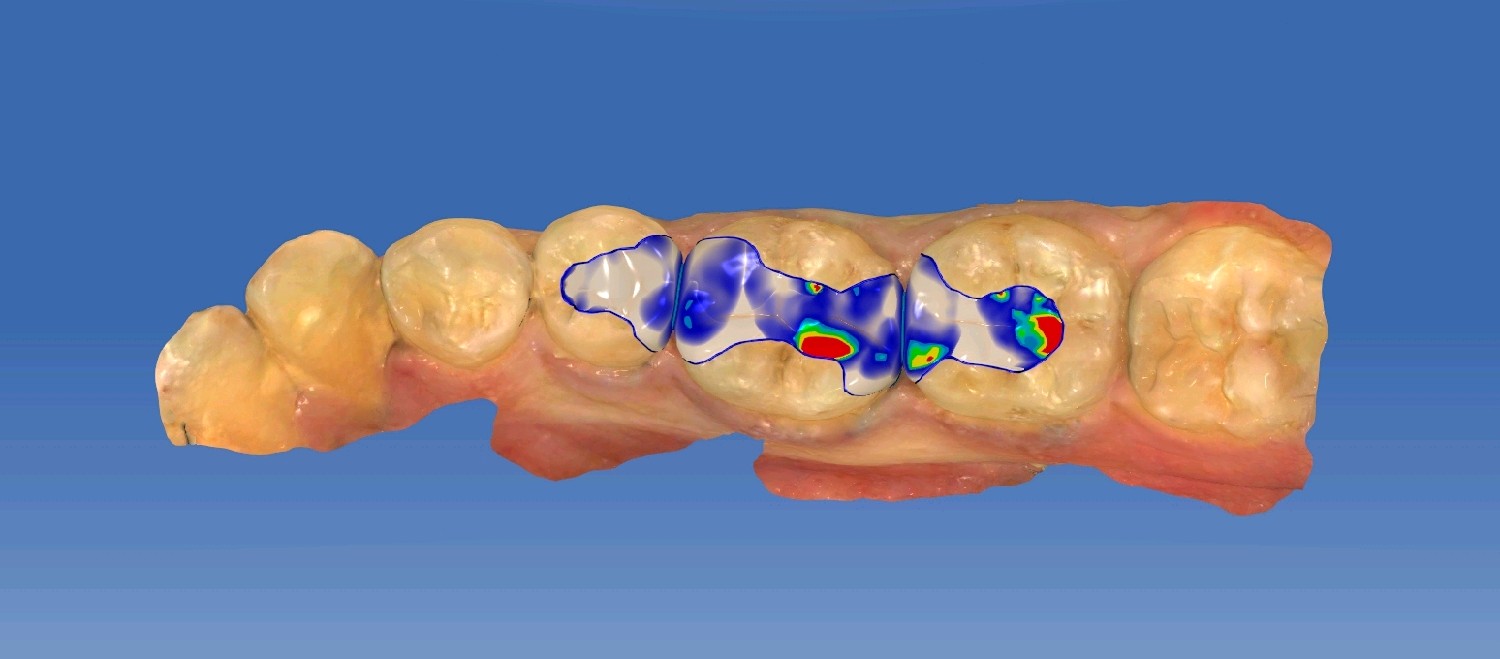

患者男24岁,自述右侧后牙食物嵌塞,无用牙线习惯。检查发现14,15,16,45,46 ,47邻颌面龋坏,探(-),扣(-),冷测正常,龋坏至牙本质中层,余无特殊。

治疗计划:嵌体修复

食物嵌塞为细菌提供了良好的滋生环境,容易导致细菌大量繁殖,产生酸性物质,从而增加蛀牙的风险。最好是用嵌体修复,能更好的恢复牙体的形态和功能。想要有一口好牙齿,做起来也不难。但是,单单口腔清洁这件小事,大多数人都没做好。你以为刷遍了牙齿的每个角落,但可能只刷了一半的牙。刷毛无法有效进入牙缝隙刷牙后仍有食物残渣等残留于牙齿邻面部位导致邻面龋坏。平时不易察觉,需要定期检查,为了更恢复邻接关系,预备制作嵌体,更好的恢复了牙体形态,增加了固位力,恢复正常的邻接关系,可以得到更好洁。基牙预备后,通过德国西诺德 CEREC ,当日完成即可佩戴,患者满意。